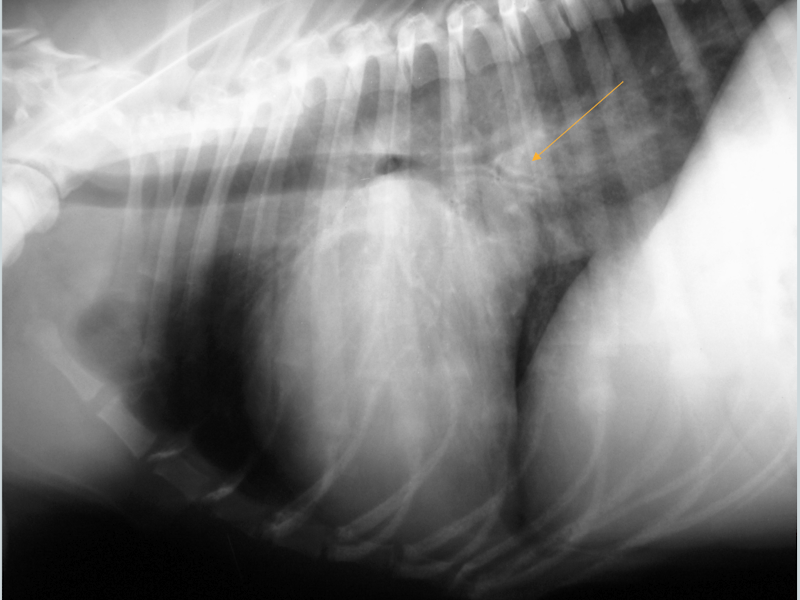

What condition is this showing in a dog? How would it differ in a cat?

Cardiogenic edema (perihilar distribution)

Cat: would look patchy and mulitfocal anywhere (see image)